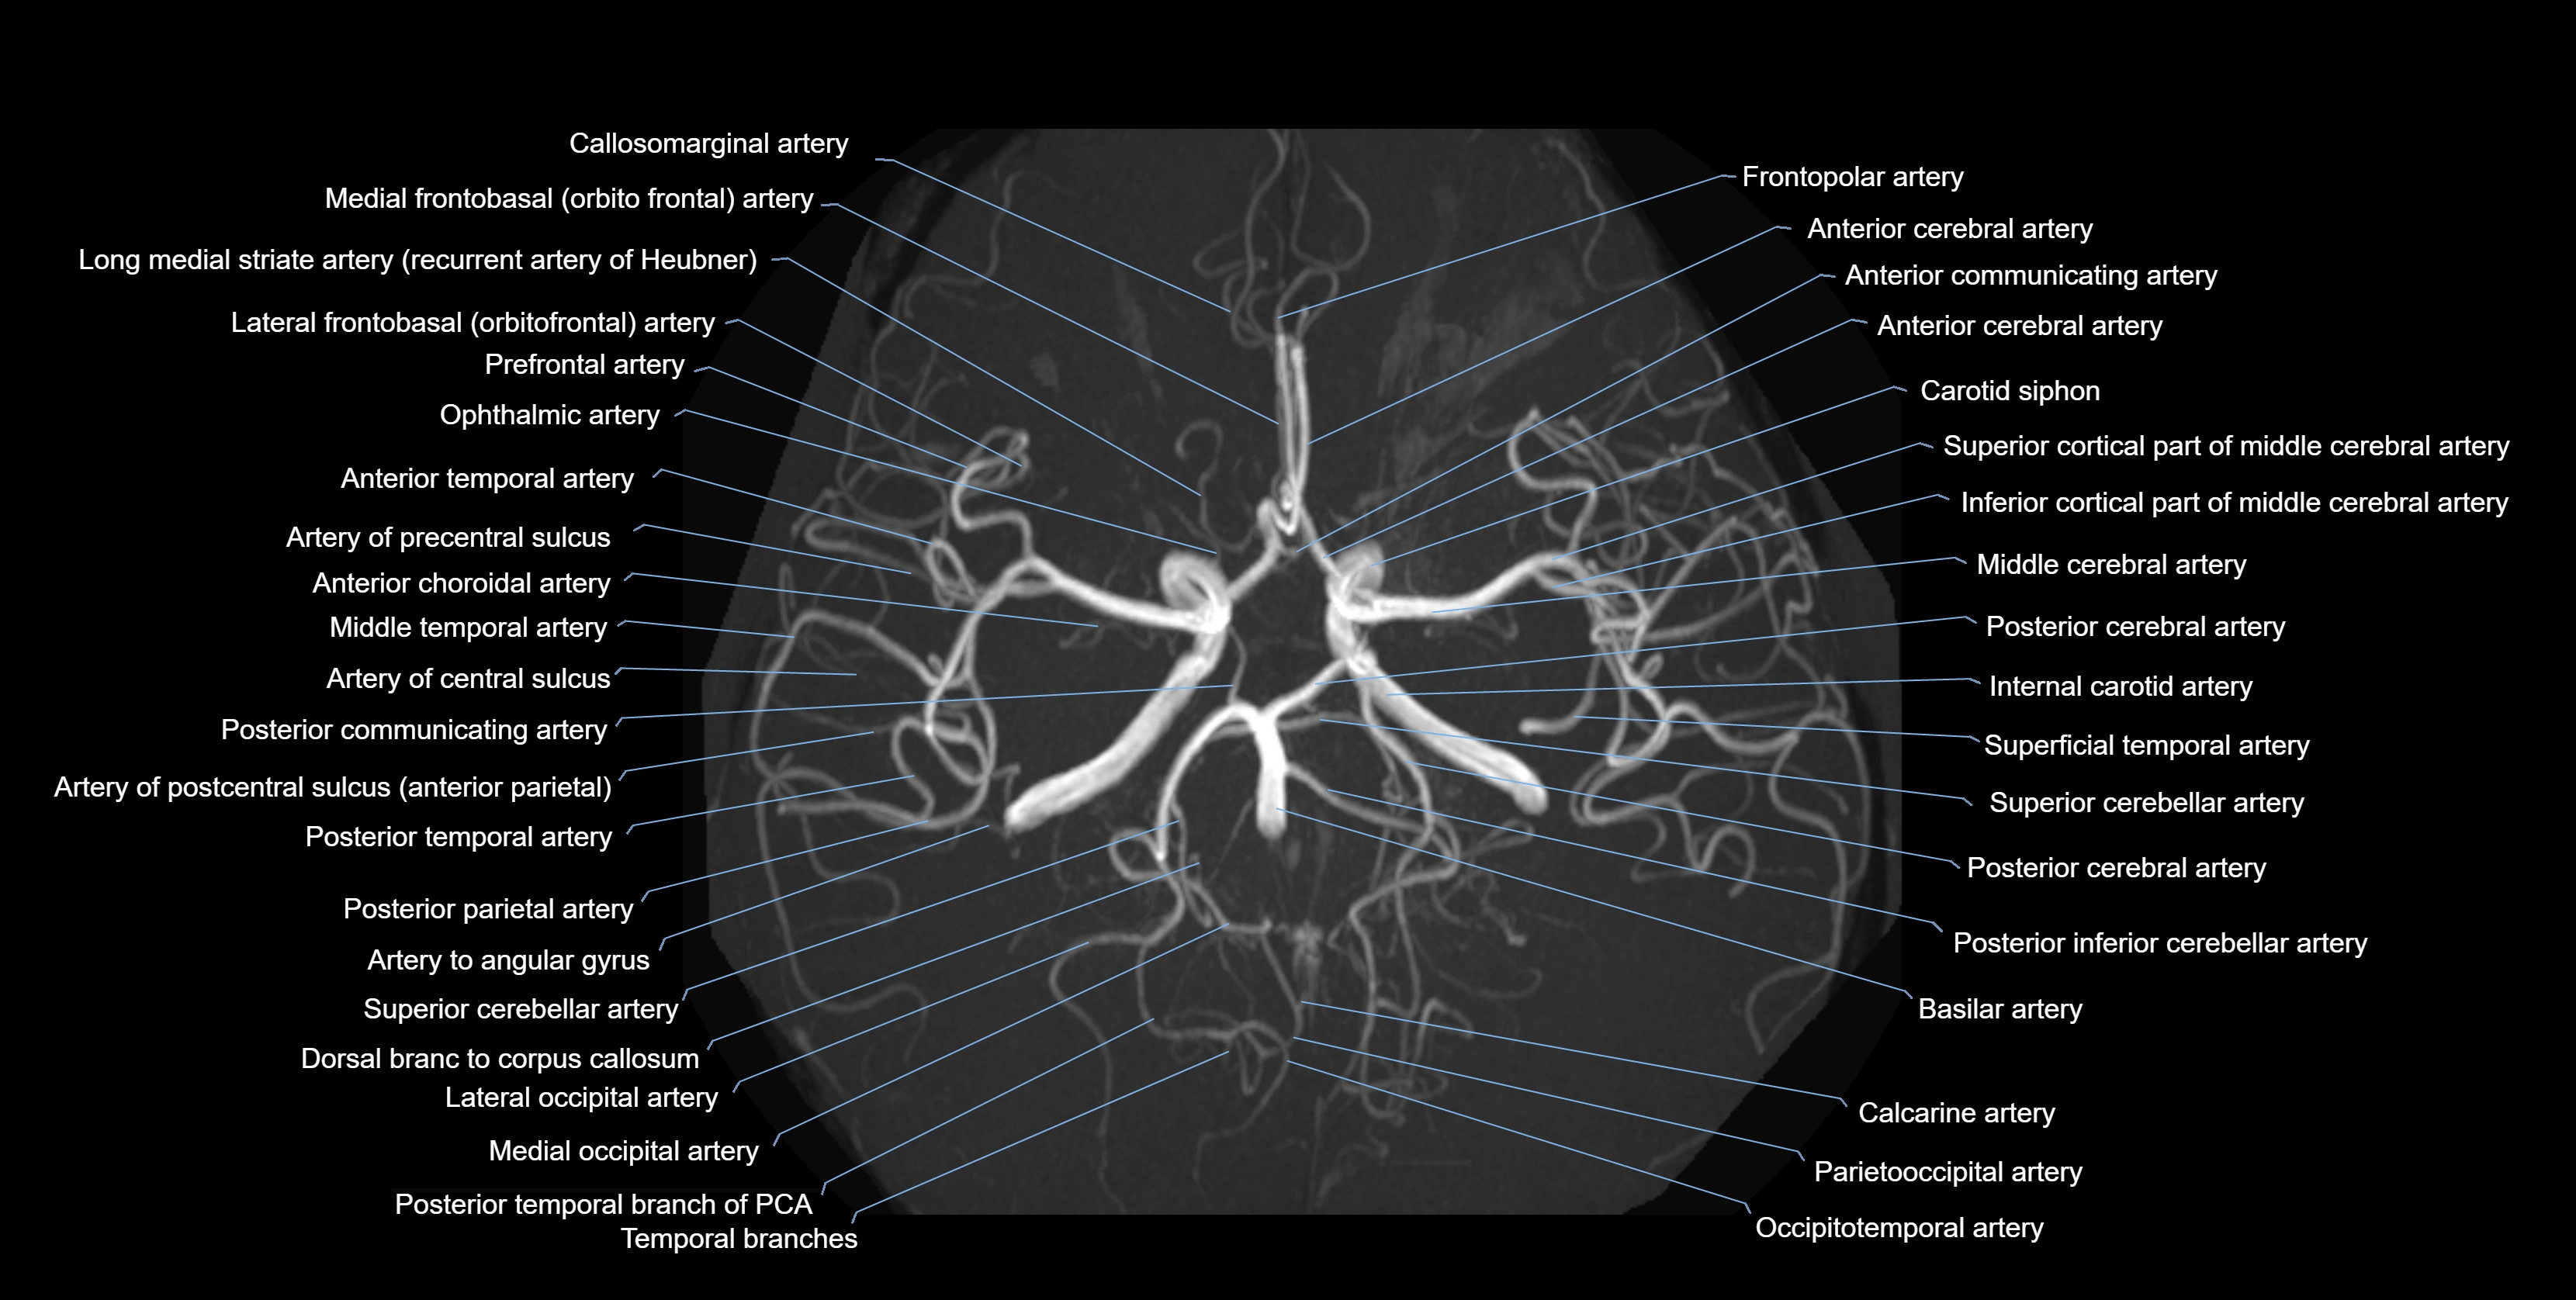

MRA (Magnetic Resonance Angiography):

• Flow-related enhancement makes the AChA appear as a bright, linear vascular signal against suppressed background

• High sensitivity for origin and proximal course; distal branches may be too small to resolve

• Detects stenosis, occlusion, aneurysm, AVM feeders

• Visualized from ICA origin along optic tract toward choroid plexus

• 3D reconstructions depict its course and relation to adjacent arteries

• Gold standard for identifying aneurysms, occlusion, or vascular anomalies